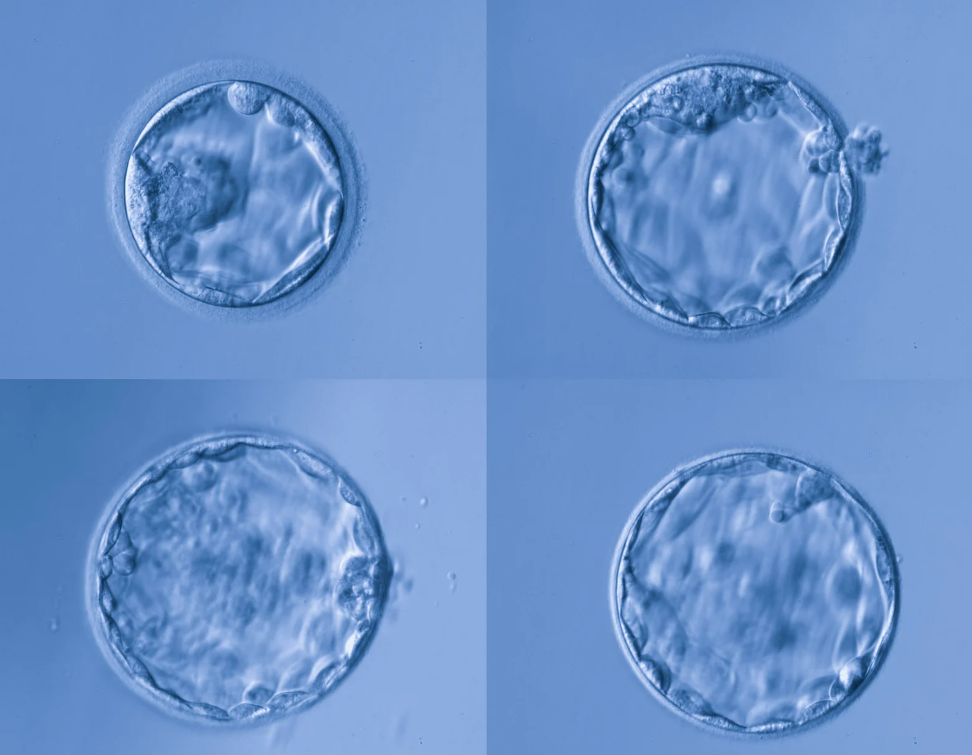

- Day 5: Around 100–200 cells — now a blastocyst, with a fluid cavity and distinct inner and outer layers.

By Day 5, the embryo has reached the blastocyst stage — a beautiful, self-organizing structure. The inner cell mass becomes the baby, and the outer layer (trophectoderm) becomes the placenta.